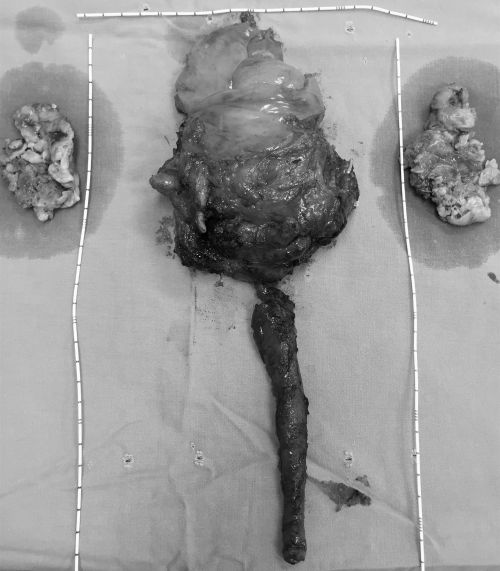

第一次手术切下的全膀胱、全尿道、部分输尿管及盆腔淋巴结。

2020年19日,泌尿三科段燚星主任医师、郭玺副主任医师团队,在全麻下为其施行“腹腔镜下膀胱癌根治性切除、双侧输尿管部分切除、全尿道切除、扩大盆腔淋巴结清扫、回肠输出道术”。手术难度极高,专家团队凭借精湛的技术圆满完成。